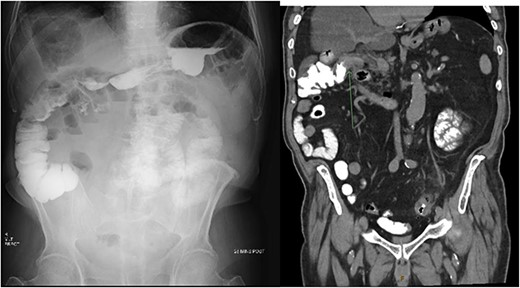

Consequently, a barium swallow and MRI abdomen were completed demonstrating the fistula between the first part of the duodenum and the ascending colon below the hepatic flexure (Figs 1 and 2). Surgical opinion and management of the patient was then sought. A subtotal cholecystectomy, partial duodenectomy, and partial resection of the colon was completed to excise the fistulous tracts. Given the patients age, he was sent to the intensive care unit for further monitoring. Day 3 postoperatively, the patient had ongoing pain and developed new tachycardia, and CT at this time demonstrated an obstruction at the colonic suture line. The patient was taken back to the operating room and a completion right hemicolectomy was performed. Histopathology from the original operation demonstrated heavy mucosal inflammation with a fistula identified histologically. The patient recovered relatively well and was able to be discharged home. The patient remained healthy and continued to be living independently in the community at 6-month follow-up.

X-ray post barium swallow demonstrating early contrast opacification of the ascending colon with coronal slice of CT confirming the presence of a fistula between the duodenum and ascending colon below the hepatic flexure.